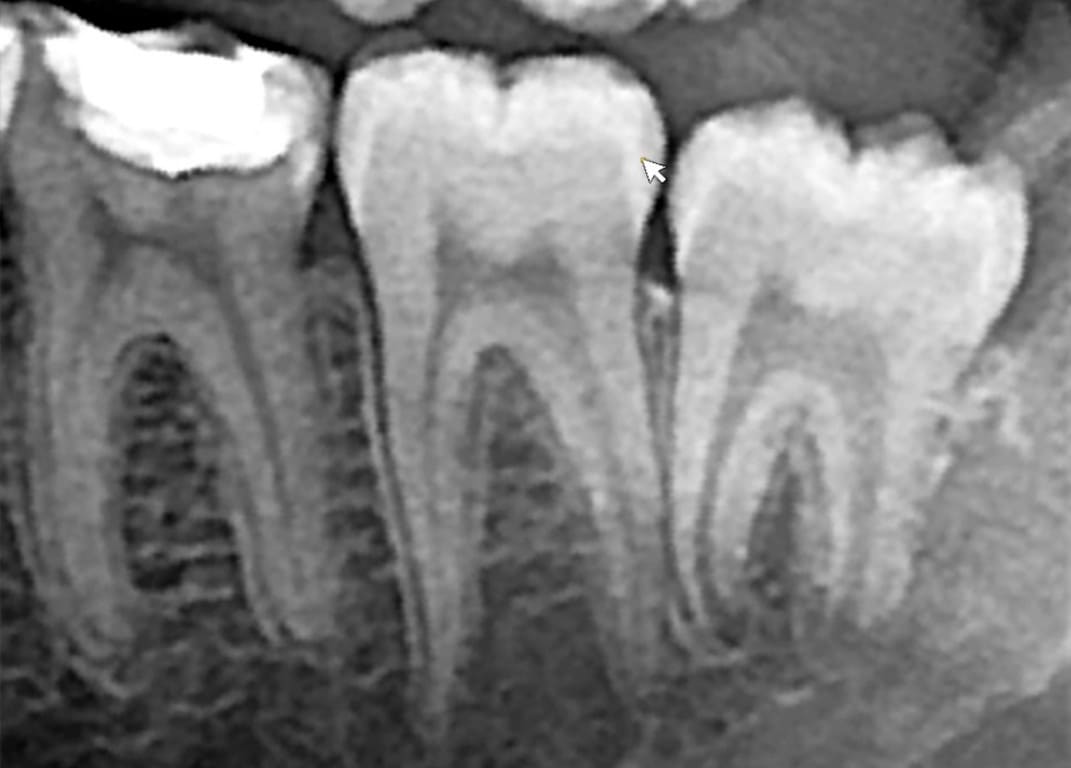

Ενδοστοματική ακτινογραφία (οπισθοφατνιακή)

Οι ψηφιακές ενδοστοματικές ακτινογραφίες αποτελούν πολύ χρήσιμο εργαλείο στην συνήθη οδοντιατρική πράξη.

Βοηθούν στην οδοντιατρική διάγνωση είτε αυτή αφορά καθαρά την κατάσταση των δοντιών, είτε την ύπαρξη περιακροριζικών αλλοιώσεων, ή και τον έλεγχο του ύψους του οστού σε περιοδοντίτιδες.

Αποτελούν ακόμη ένα χρήσιμο εργαλείο κατά την διάρκεια των οδοντιατρικών επεμβάσεων όπως για τον καθορισμό του μήκους των ριζών στις ενδοδοντικές θεραπείες (απονευρώσεις).